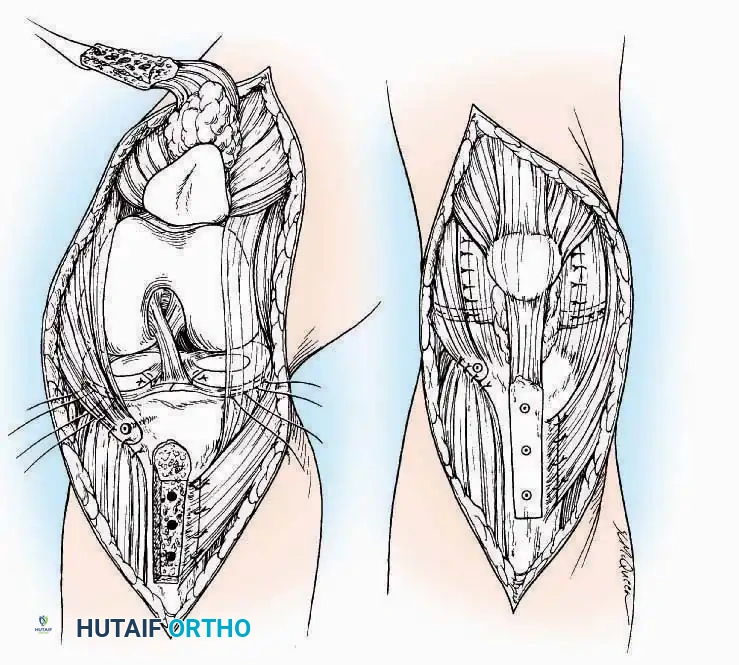

Kocher Approach (Curved L)

Indications: Complete excision of the calcaneus (calcanectomy) for malignant tumors or recalcitrant osteomyelitis.

Surgical Technique:

* Incision: Incise the skin over the medial border of the Achilles tendon, starting 7.5 cm proximal to the calcaneal tuberosity. Extend it distally to the inferoposterior aspect of the tuberosity, curve it transversely around the posterior heel, and continue distally along the lateral surface of the foot to the tuberosity of the fifth metatarsal.

* Deep Dissection: Divide the Achilles tendon directly at its insertion and carry the dissection down to the bone.

* Enucleation: To reach the superior surface, free all tissues beneath the severed Achilles tendon. The calcaneus can then be enucleated subperiosteally or extraperiosteally depending on the oncologic or infectious margins required.